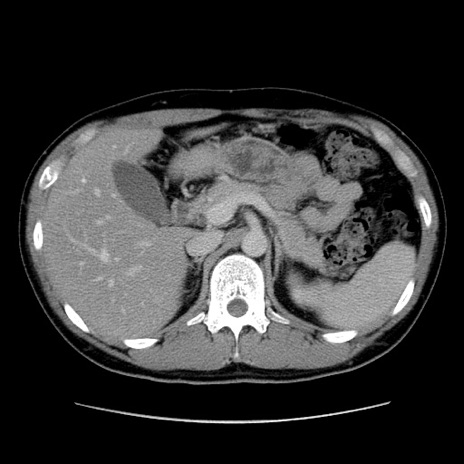

冠状断像

【症例】20歳代 男性

【主訴】心窩部痛

【現病歴】今朝より上腹部痛あり。一旦軽快していたが再度出現したため救急要請。昨日夕に白身の魚を含む刺身を食べた。

【身体所見】BP 136/89mmHg、HR 74/min、BT 37.0℃、腹部:膨満、軟、心窩部に圧痛あり。反跳痛なし、筋性防御なし、腸雑音やや亢進あり。

【データ】WBC 17700、CRP 0.48